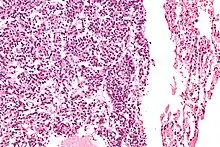

| Micrograph of a typical pulmonary carcinoid tumour. | |

The definitive diagnosis is rendered by a microscopic examination, after excision. Typical carcinoids have cells with stippled chromatin and a moderate quantity of cytoplasm. They typically have few mitoses and lack necrosis. By definition, they are greater than 4 mm in largest dimension; smaller lesions are referred to as pulmonary carcinoid tumourlets.